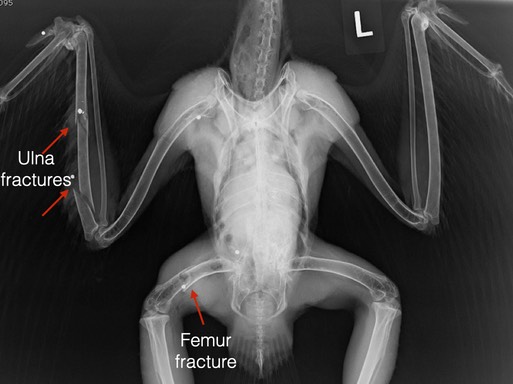

Red-tailed Hawk 20-563 from Wapato, WA was number two. The x-ray below leaves no doubt as to the cause of the hawk’s multiple fractures (6 shotgun pellets are visible). When the accompanying damage in the right wrist, elbow and hip were considered, euthanasia was the most humane option.

The third gunshot hawk was Red-tailed Hawk 20-565 from Eltopia, WA. There are 9 pellets or pellet fragments in the first x-ray (4 in the body, 1 in each wingtip, 1 in the neck and 2 in the head). The second x-ray shows 5 more pellets in the left leg and foot. There are multiple fractures in the major and minor metacarpals in the left wing. The wing has been splinted to immobilize the fractures. The hawk appears to be blind in his left eye. The hearing in the left ear may also be affected.